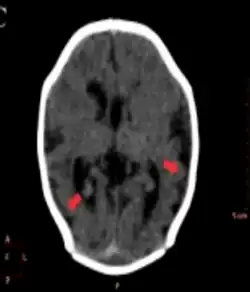

Different imaging modalities are commonly used for diagnosis. While computed tomography (CT) provides higher spatial resolution imaging of the brain, cerebral cortex malformations are more easily visualized in vivo and classified using magnetic resonance imaging (MRI) which provides higher contrast imaging and better delineation of white and gray matter.[7]

Diffuse pachygyria (a mild form of lissencephaly) can be seen on an MRI as thickened cerebral cortices with few and large gyri and incomplete development of the Sylvian fissures.[3]